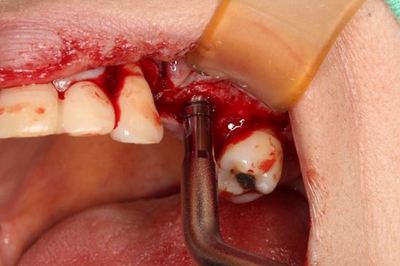

![]()

病変の大きな歯の抜歯後に円形の骨欠損があります。